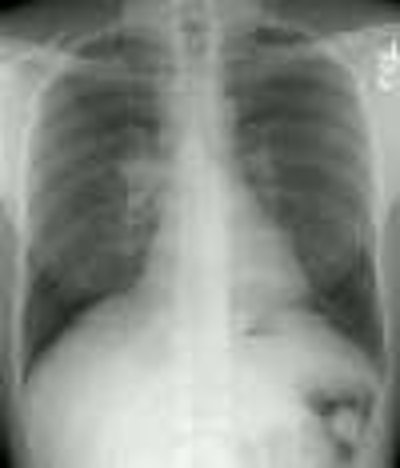

The patient presented with cough and URI symptoms. The CXR demonstrated right paratracheal and bilateral hilar adenopathy. (Click on small image to view larger radiograph)